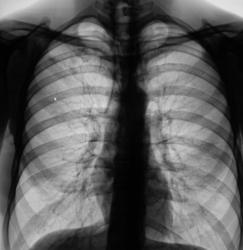

Флюорограмма 2007 год.

Флюорограмма 2008 г.

Флюорограмма 2009 г.

В 2008 году пациент был взят на контроль и был вызван на дообследование, но "вдруг исчез" из населенного пункта. Но в этом году, а именно сегодня пациента удалось дообследовать.

Че ту долго думать Суперрр раскручивать надо, на первом месте туберкулез, конечно.

Инфильтративный туберкулёз справа

инфильтративный туберкулёз.